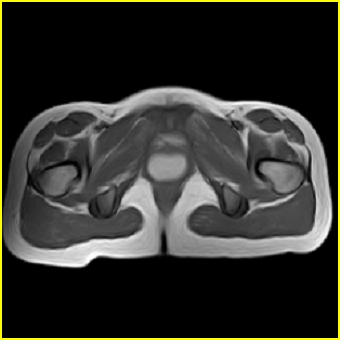

女、15岁、下腹疼痛2天,排尿困难1天。查体:处女膜闭锁,距处女膜约4至5cm处扪及一约5cm直径的圆形包块,张力较高,触痛明显、欠活动。b超提示子宫增大伴宫内增强回声团。

影像意见:子宫直肠陷凹积血。

更正影像意见:阴道积血。

处女膜闭锁,阴道积血

处女膜闭锁,阴道积血,子宫积血.

阴道积血,子宫积血.

子宫及阴道积血。

处女膜闭锁,伴子宫及阴道积血.